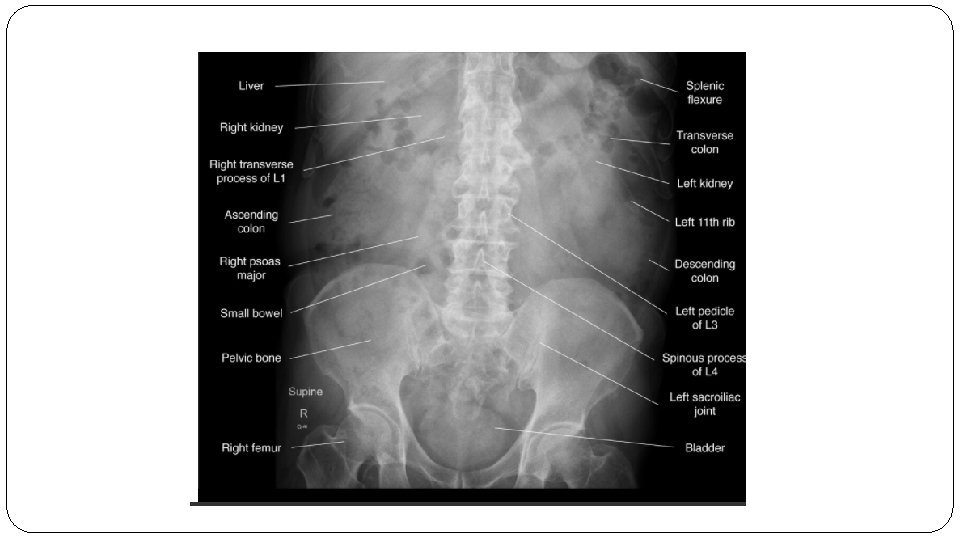

Normal abdominal X-ray

Location Small bowel Large bowel Central Peripheral Wall Pattern Encircling valvulae conniventes visible depending on degree of air filling/distention. Haustral folds interspaced with Plicae semilunaris Size 6 cm diameter (caecum 9 cm) 3 cm diameter